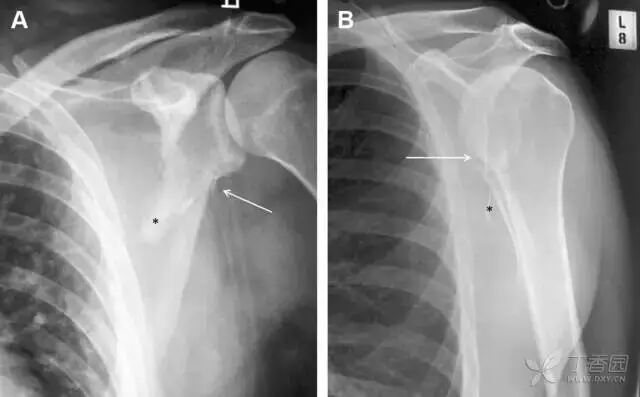

25肩胛骨骨折

肩胛骨几何形状复杂,受到邻近其它骨性结重叠阻挡,且肩胛骨骨折少见,因此容易漏诊。当存在解剖变异时,诊断更为困难。

图 3 肩胛骨骨折正侧位片:由于骨块的叠加,(A)前后位片示「V」形高密度影(*),肩胛颈下方可见骨皮质碎片(箭头);(B)侧位片示骨皮质中断,骨折段移位,但由于肱骨的重叠遮挡,决断往往比较困难

26喙突骨折

喙突骨折可发生于直接暴力、肩关节脱位过程的肱骨头撞击、以及撕脱骨折(肱二头肌短头、喙肱肌)。

其中喙突基底部骨折最多见,常发生于直接暴力或肱骨头前脱位,骨折可延伸至关节盂。

而撕脱骨折多为喙突尖部的骨折。需要加拍腋位和 Stryker 位片(X 射线束以喙突为中心并头倾 10°,手臂外展,这样可以避开骨性结构的阻挡)。

有时,负重位片可发现并存的肩锁关节脱位,将有助于诊断。

图 4 喙突骨折。66 岁男性患者,猎枪射击后右肩前方疼痛。(A)内旋位前后位片投影隐约可见喙突基底部骨折(白色箭头),(B)外旋位前后位片投影结构存在重叠,(C)腋位投影时可良好显示。(D~F)喙突骨折伴 Hill-Sachs 损伤:肩关节脱位后慢性疼痛,喙突骨折块(*)向前外侧移位(双箭头),在外旋前后位(D)及腋位(E)片上均可显示,在内旋位前后位(F)片上,喙突被遮挡,但可见肱骨头 Hill-Sachs 损伤。(G、H)喙突骨折伴肩锁关节脱位,肩锁关节分离(白色双箭头),而喙锁间距正常(黑色的双箭头),应警惕喙突骨折。(I)喙突与肩峰骨化中心:对于未成年人,喙突与肩峰骨化中心可同时存在,易与骨折混淆,此时,拍对侧的 X 线片对比将有助于诊断。

27肩峰骨折

肩峰骨折为高能量损伤,多由直接暴力导致,好发于中青年患者,多伴有肩关节其它结构损伤。有必要拍摄 Rockwood 位(前后位片,X 线束尾倾),特别有利于显示肩峰下部及肩峰下间隙。

图 5 肩峰骨折。内旋位前后位(A)片上,骨折线几乎被喙突完全遮挡, 但是在标准前后位(B)和腋位(C)片上可见骨折线